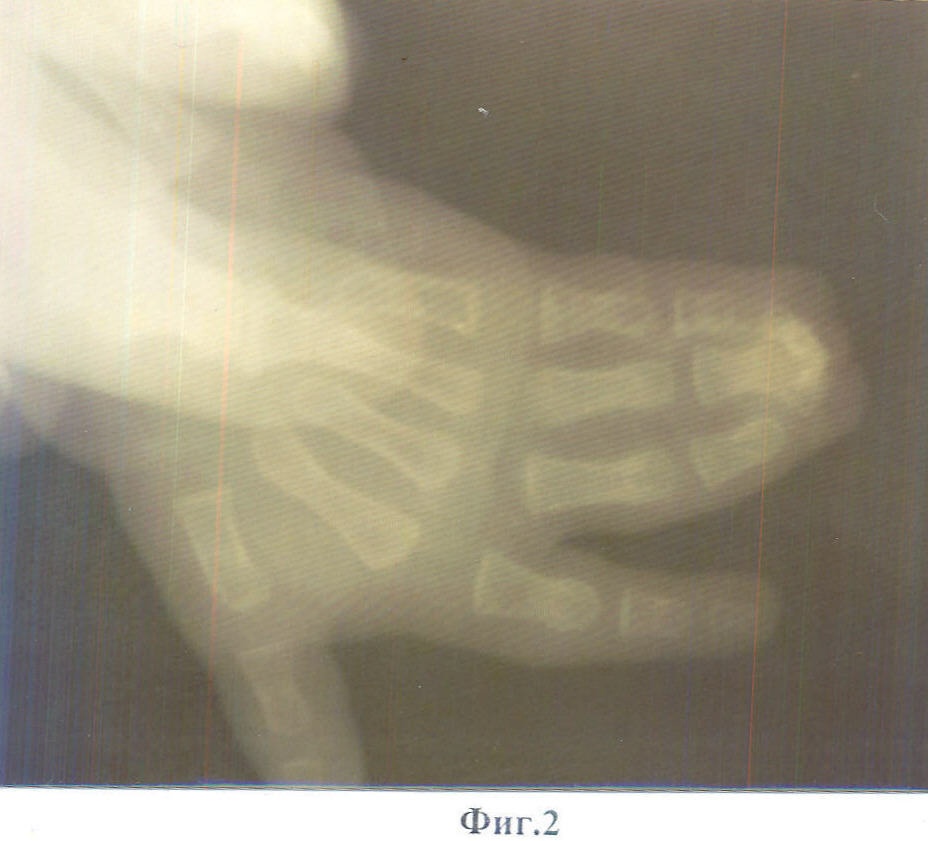

Способ поясняется фотографиями: на фиг.1 показан вид кисти до операции; на фиг.2 – рентгенограмма до операции; на фиг.3 – вид пальцев, разделенных до головок основных фаланг, со стороны ладони; на фиг.4 – вид разделенных пальцев со стороны тыла ладони; на фиг.5 – вид кисти после устранения деформации с фиксацией фаланг пальцев спицами; на фиг.6 – выкраивание полнослойного кожного лоскута на предплечье; на фиг.7 – рентгенограмма кисти после операции; на фиг.8 – вид кисти после операции. Способ осуществляется следующим образом.